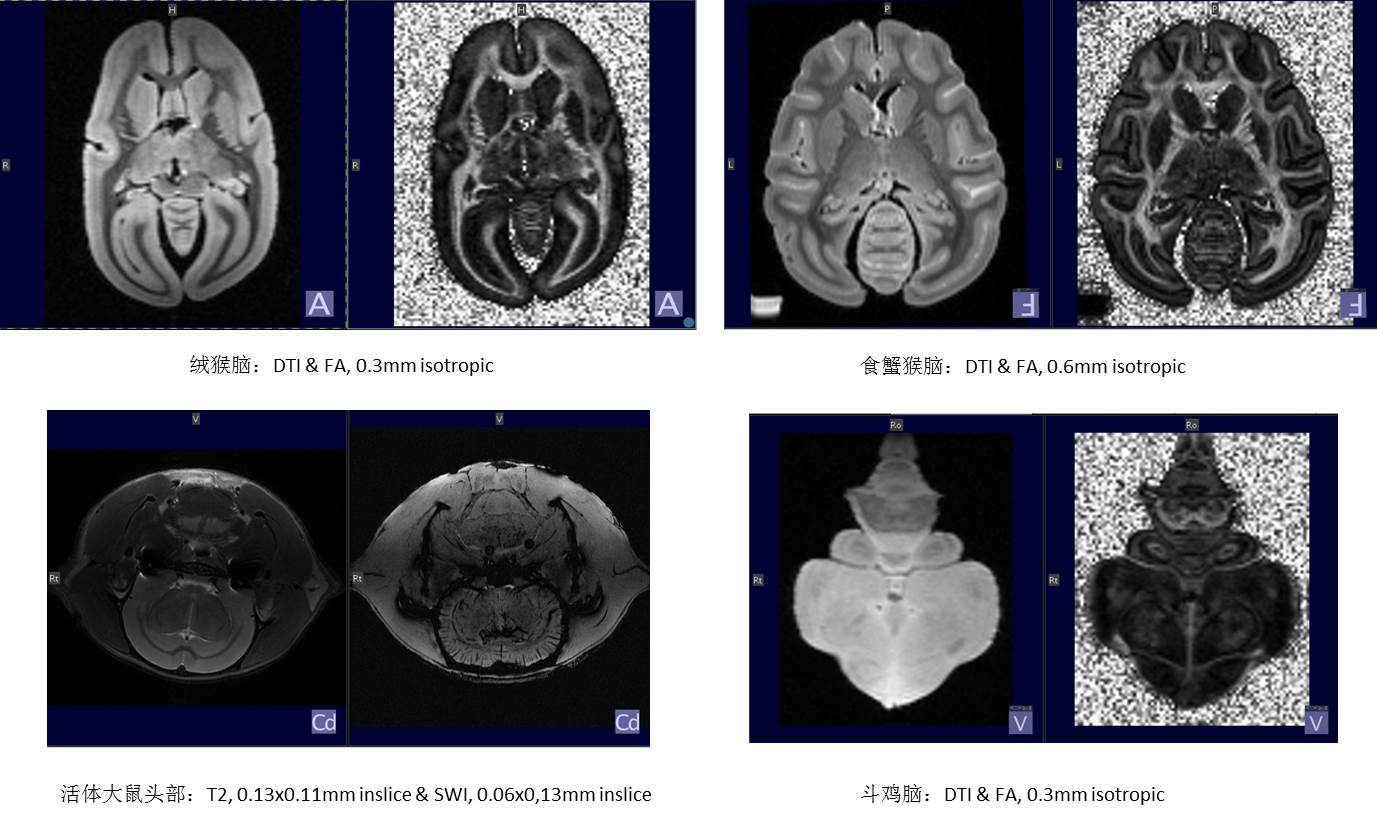

部分动物成像结果: